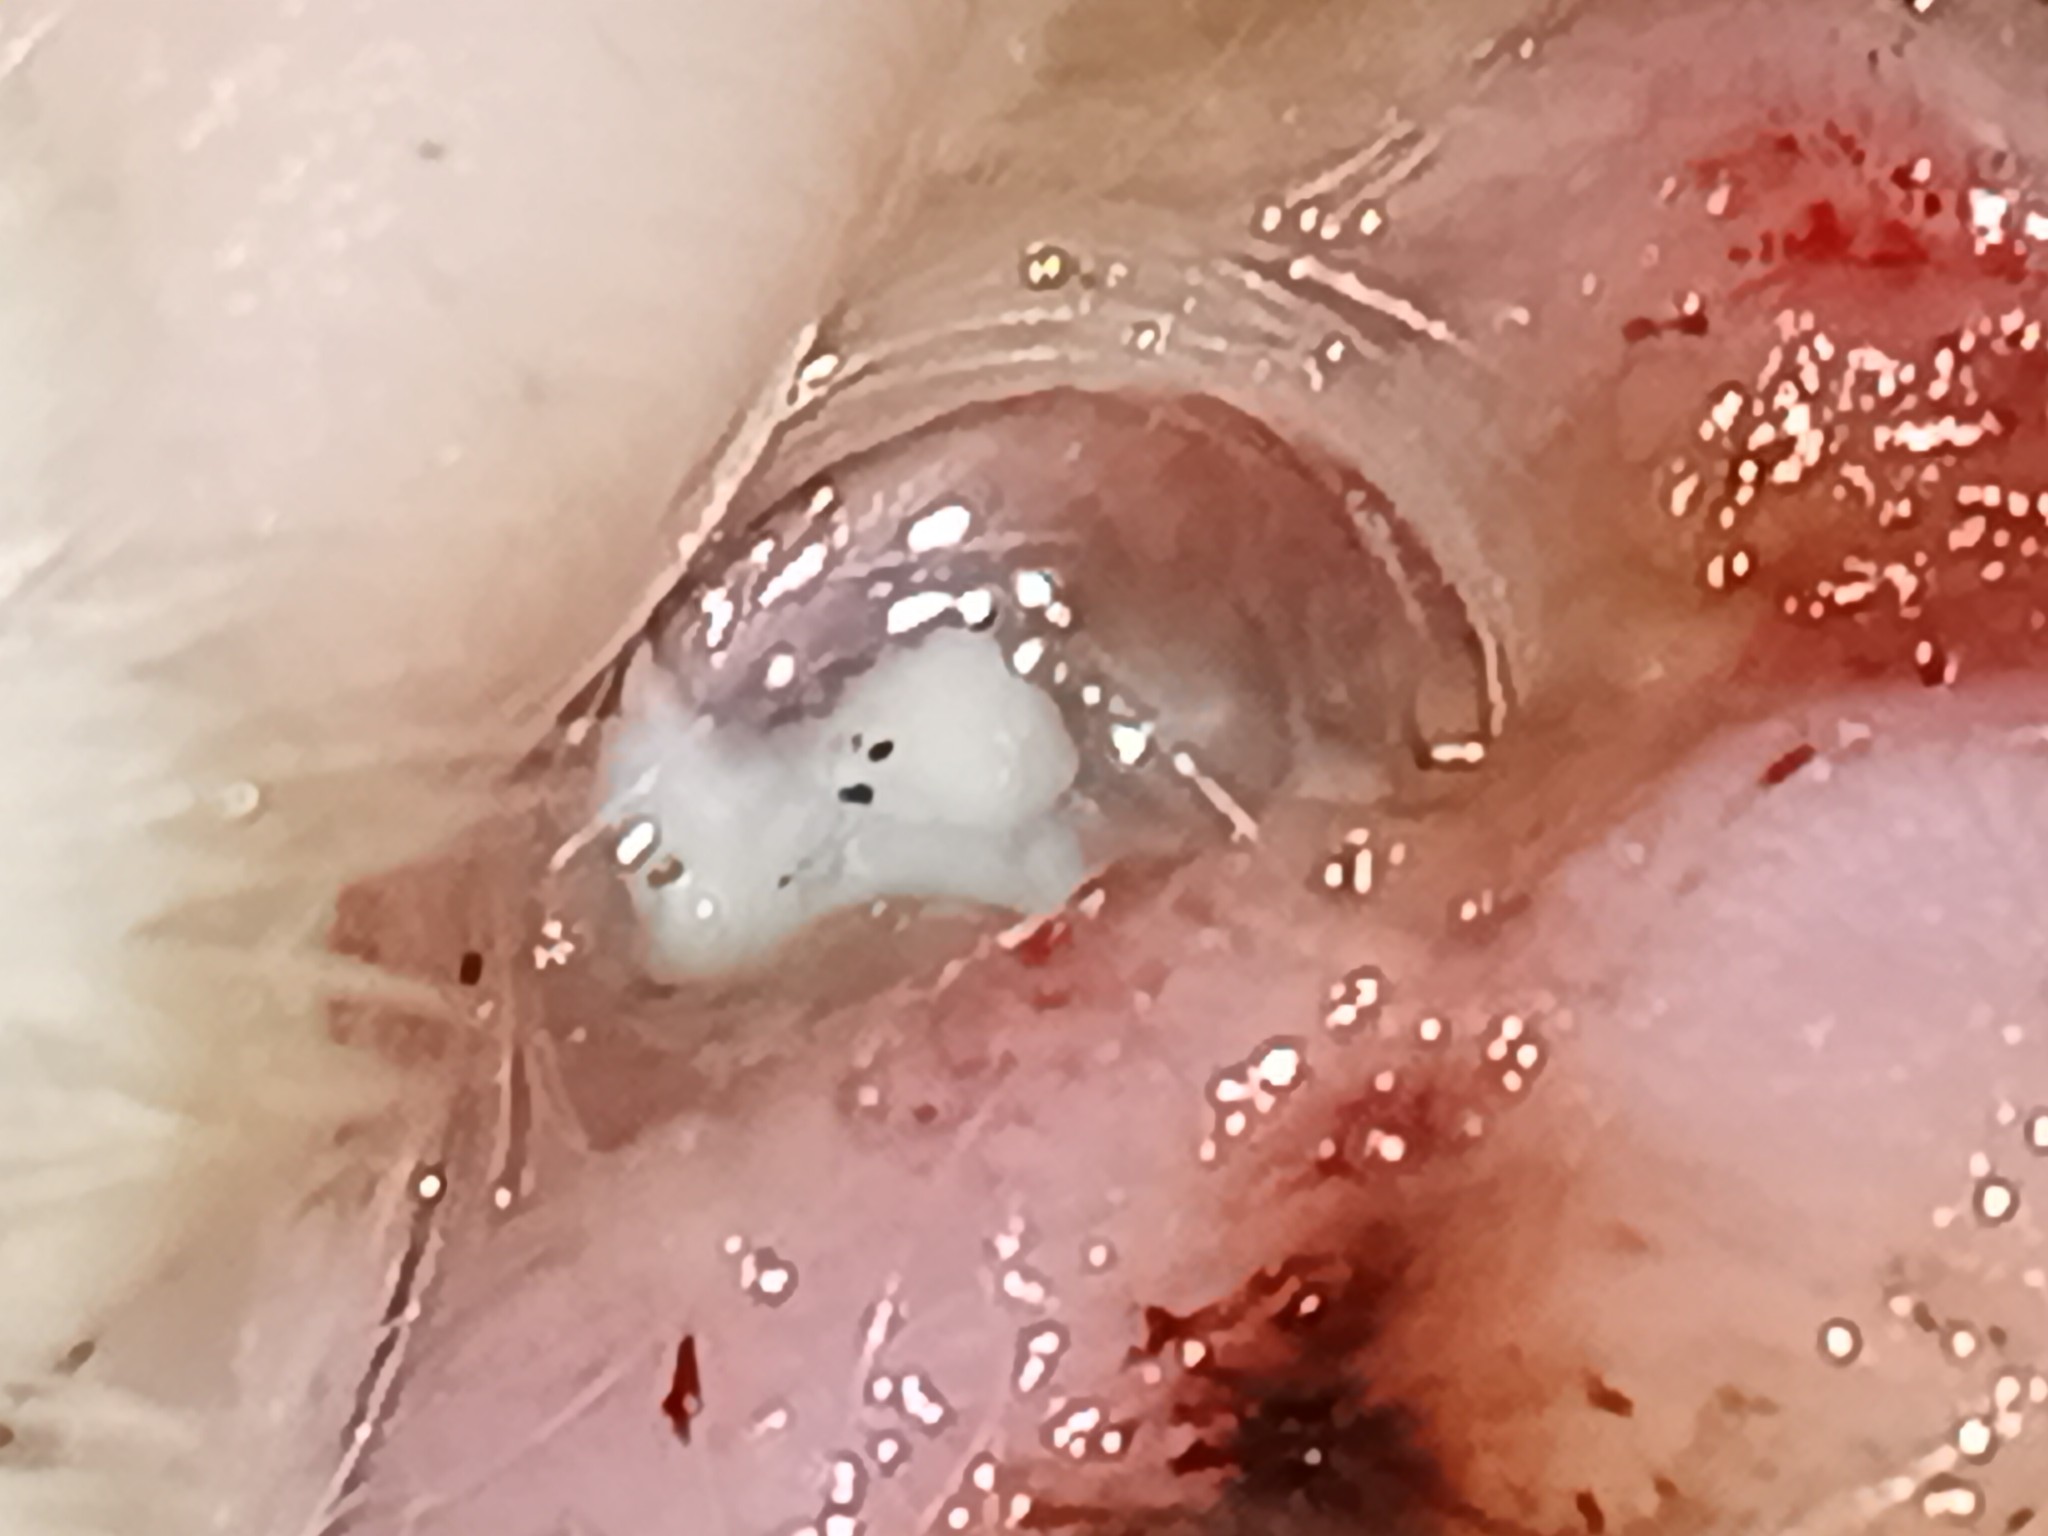

คือแมวเราโดนอะไรบาดมาไม่รู้แล้วมันลึก ตอนแรกเหมือนไม่ลึกมากแต่น่าจะโดนหนองกินมันเลยลึกกว่าเดิม แล้วแมวเราไม่ค่อยเลียแผลเพราะน่าจะเจ็บเลยกางเล็บเลียไม่ได้ จะขอตังแม่เอาไปรักษาก็ไม่กล้าเพราะแม่น่าจะไม่พอใจที่เอาเงินไปรักษาแมว แม่อาจจะมองว่ามันไร้สาระแล้วกลัวเขาโมโหด้วย

แผลประมาณนี้สามารถเปิดรับบริจาคได้ไหมคะ